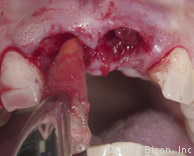

Подготовка к установке постоянной конструкции

Произведены послабляющие разрезы

Установка готовых конструкций